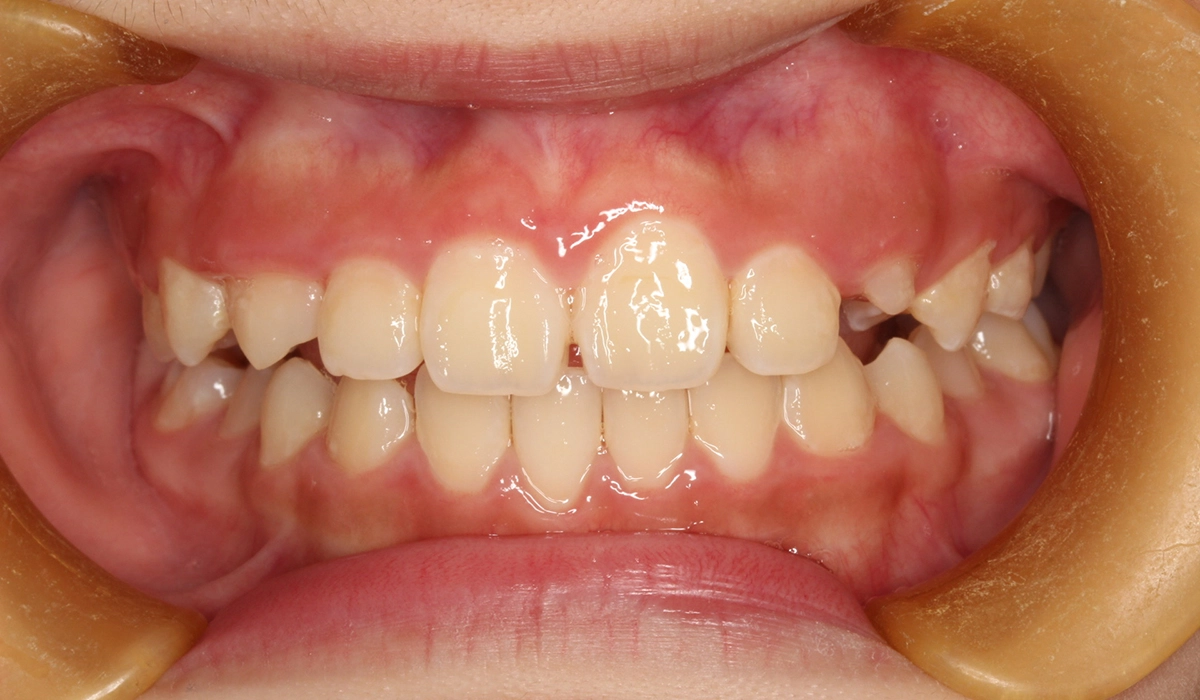

術前:正面

今回ご紹介する患者様は、前歯の捻れを気にされており、矯正検査後叢生Ⅰ級と診断いたしました。

主訴 前歯の捻れが気になる

治療期間 70カ月

治療費用 453,600円(税込)※2019年時治療費

治療内容 前歯の捻れを気にされており、矯正検査後叢生Ⅰ級と診断いたしました。